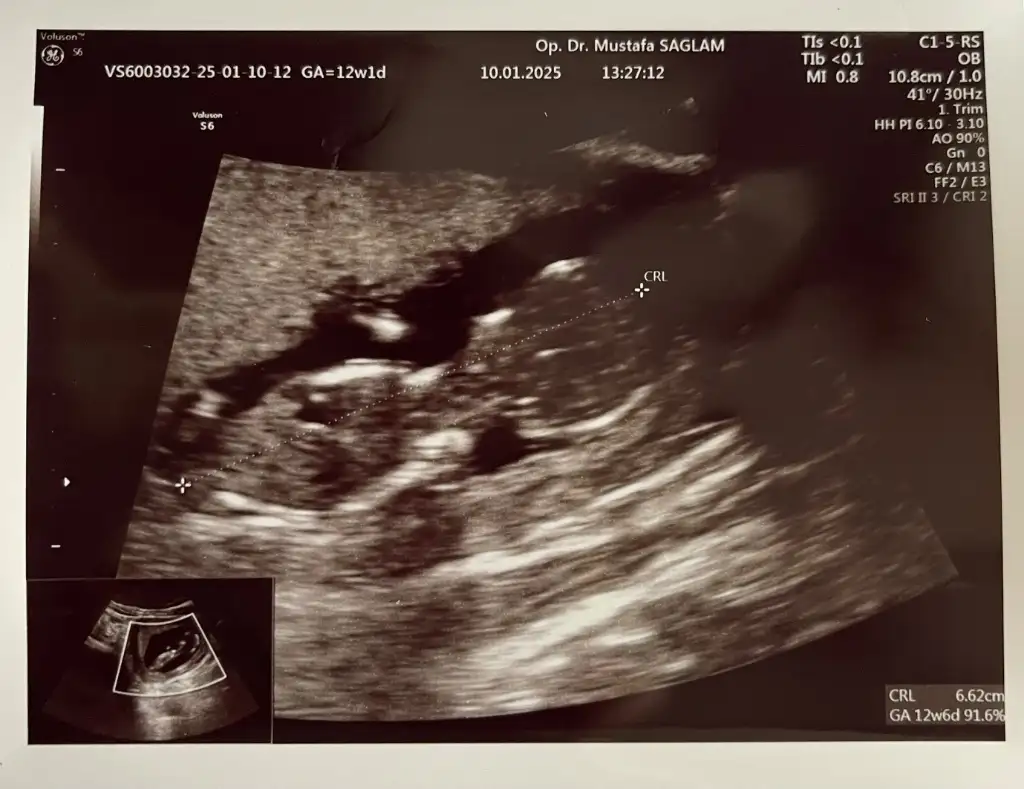

Çok net görünüyor erkek. Hayırlı olsunMerhabalar 12+5 haftalik hamileyim doktorum bugun cinsiyeti söyledi ama bana biraz erken gibi geliyor. Görsellerden tahmin edebilcek var mı acaba. Doktorum bakarken sürekli göbek kordonu bacak arasında dedigi icin emin olamadım. Doktorumun demesine göre oglum olcakEki Görüntüle 3528053

Canım banada bakar mısınızKafa yapısı bana kız gibi geldi ama doktor daha iyi bilir tabi ayrıca yine de erken bence tam net öğrenmek için 16 haftalıkken bir daha görünün doktora

Direk çıkıntı var bence hayırlı olsun şimdidenMerhabalar 12+5 haftalik hamileyim doktorum bugun cinsiyeti söyledi ama bana biraz erken gibi geliyor. Görsellerden tahmin edebilcek var mı acaba. Doktorum bakarken sürekli göbek kordonu bacak arasında dedigi icin emin olamadım. Doktorumun demesine göre oglum olcakEki Görüntüle 3528053